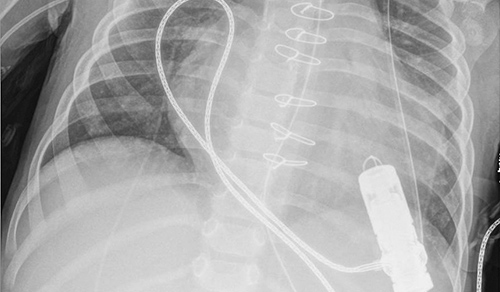

At the Children's Hospital of New York, our neonatologists from Columbia and Weill Cornell Medicine care for the sickest neonates and infants while providing hope and comfort to their families. The exceptional expertise of our clinicians and deep research continues to have a substantial impact in neonatology, including gentle ventilation of neonates and how to support neurodevelopment and growth.

Neonatology